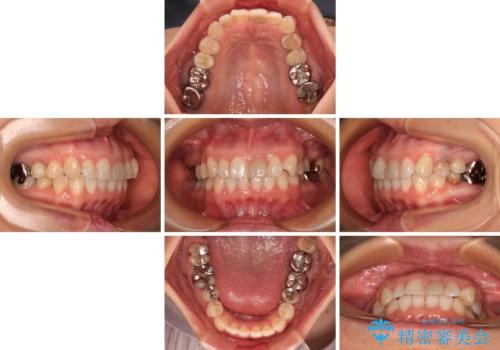

- 上下前歯のデコボコを気にして来院された患者様です。

カウンセリングにて詳しく話を聞いたところ、一番気になっているのは下顎前歯の叢生であり、上顎犬歯はあまり気になっていないとのことでした。

矯正治療は、歯の後戻りを抑制するために、治療終了後も保定装置をしっかりと使用していただくことが必須であるため、気になっている下顎だけを整えることで、その負担を半減できると考え、下顎のみの部分矯正として治療を行うこととしました。

装置としては、叢生の程度が強くなかったため、インビザラインの廉価版であるモデレート・パッケージを使用することとしました。

当院では治療前の歯列が整っていない限り、下顎前歯の舌側をワイヤーで固定するようにしています。下顎のみの部分矯正としたことで、マウスピース保定の負担を軽減することができました。

上顎は、失活して歯の色が変色しているため、将来的に補綴治療で自然な口元に仕上げていきたいとのことでした。